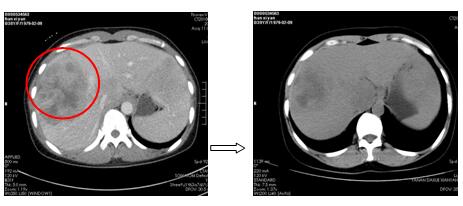

針對(duì)每一例化療患者,參照最新NCCN指南(為腫瘤診療的國(guó)際權(quán)威指南),為患者制定規(guī)范、有效的個(gè)體化化療方案。2周期化療后評(píng)價(jià)療效:其中1例肺癌肉瘤術(shù)后的胰腺占位的患者,2次化療后胰腺占位基本消失,另有1例非小細(xì)胞肺癌伴肺、心包、肝多發(fā)轉(zhuǎn)移患者,2次化療后肺部、肝內(nèi)病灶顯著縮小,其余化療患者還未到療效評(píng)價(jià)時(shí)機(jī)(指南推薦每2周期評(píng)價(jià)化療療效)。

圖2. 肺癌伴多發(fā)轉(zhuǎn)移患者,化療后肺、心包、肝臟病灶明顯縮小